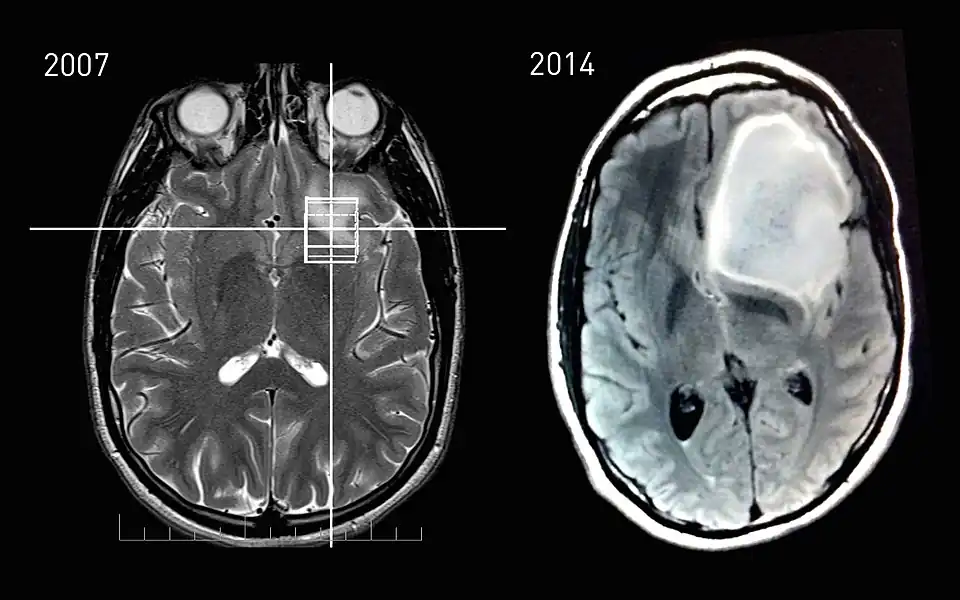

Tumor progression is the third and last phase in tumor development.[1] This phase is characterised by increased growth speed and invasiveness of the tumor cells. As a result of the progression, phenotypical changes occur and the tumor becomes more aggressive and acquires greater malignant potential. Together with the progression, more and more aneuploidy occurs. This may be evident as nuclear polymorphism.